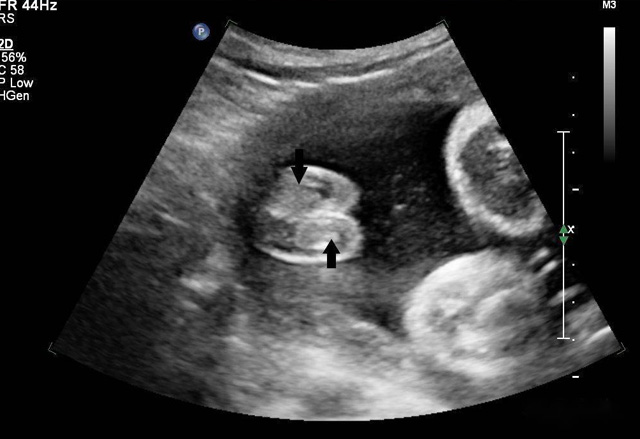

三維超聲技術可用於心髒、腹腔、婦科、產科、小器官、血栓、血管成像等多方麵。